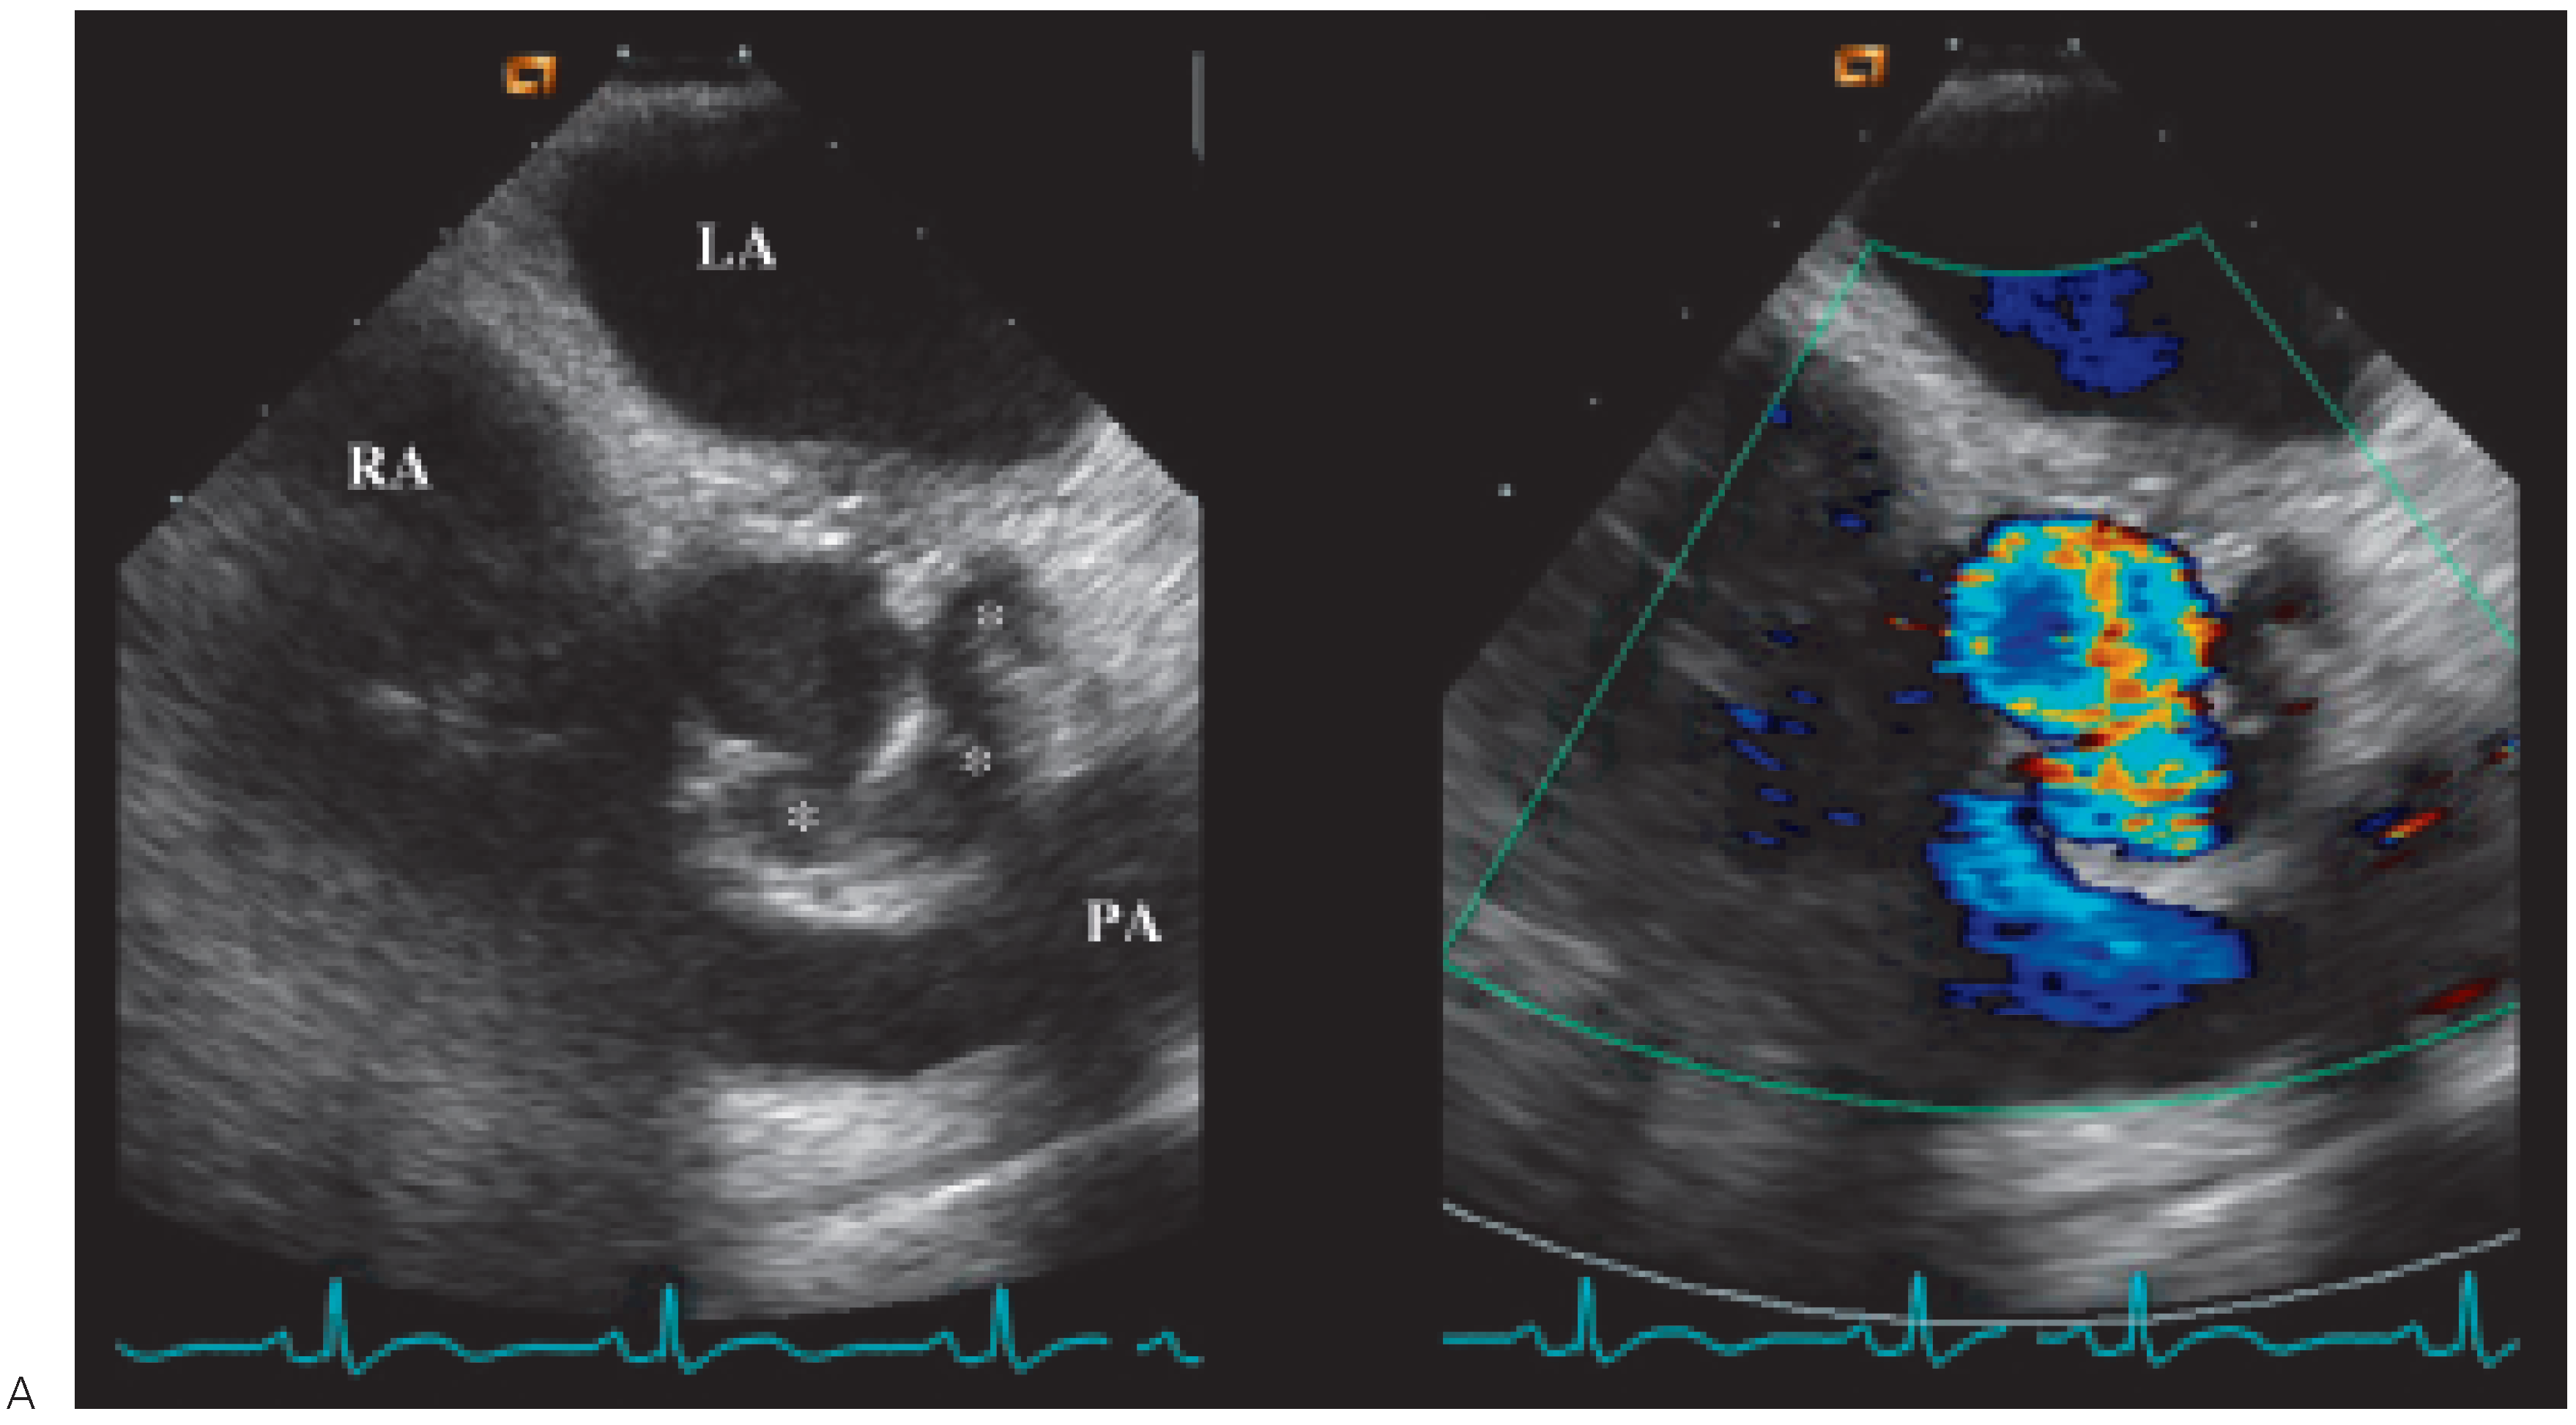

Transthoracic echocardiography was performed with only apical views available (Figure 1). It demonstrated abnormal motion of the prosthesis annulus but only a mild aortic insufficiency. Neither vegetations nor abscess were visualised. As the probability of prosthetic endocarditis was high, a transoesophageal echocardiography (Figure 2 and Figure 3) was organised immediately afterwards. It demonstrated a partially dehiscent prosthesis due to a subjacent hemicircumferential paraprosthetic abscess. This abscess has spontaneously drained, leaving a large cavity. Large vegetations were also observed on the leaflets of the bioprosthetic valve.

Figure 1. TTE apical 3 cavity. During systole, dehiscence between prosthetic annulus and septal wall.